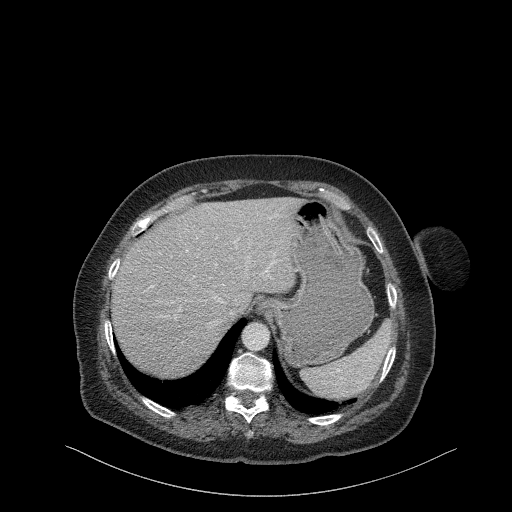

Original NATIVE CT scan (input)

Full window (WL 1023.5, WW 4095 β†’ Low βˆ’1024, High +3071)

Actual HU range: [-160.0, 240.0]

Mediastinum window (WL 40, WW 400 β†’ Low βˆ’160, High +240)